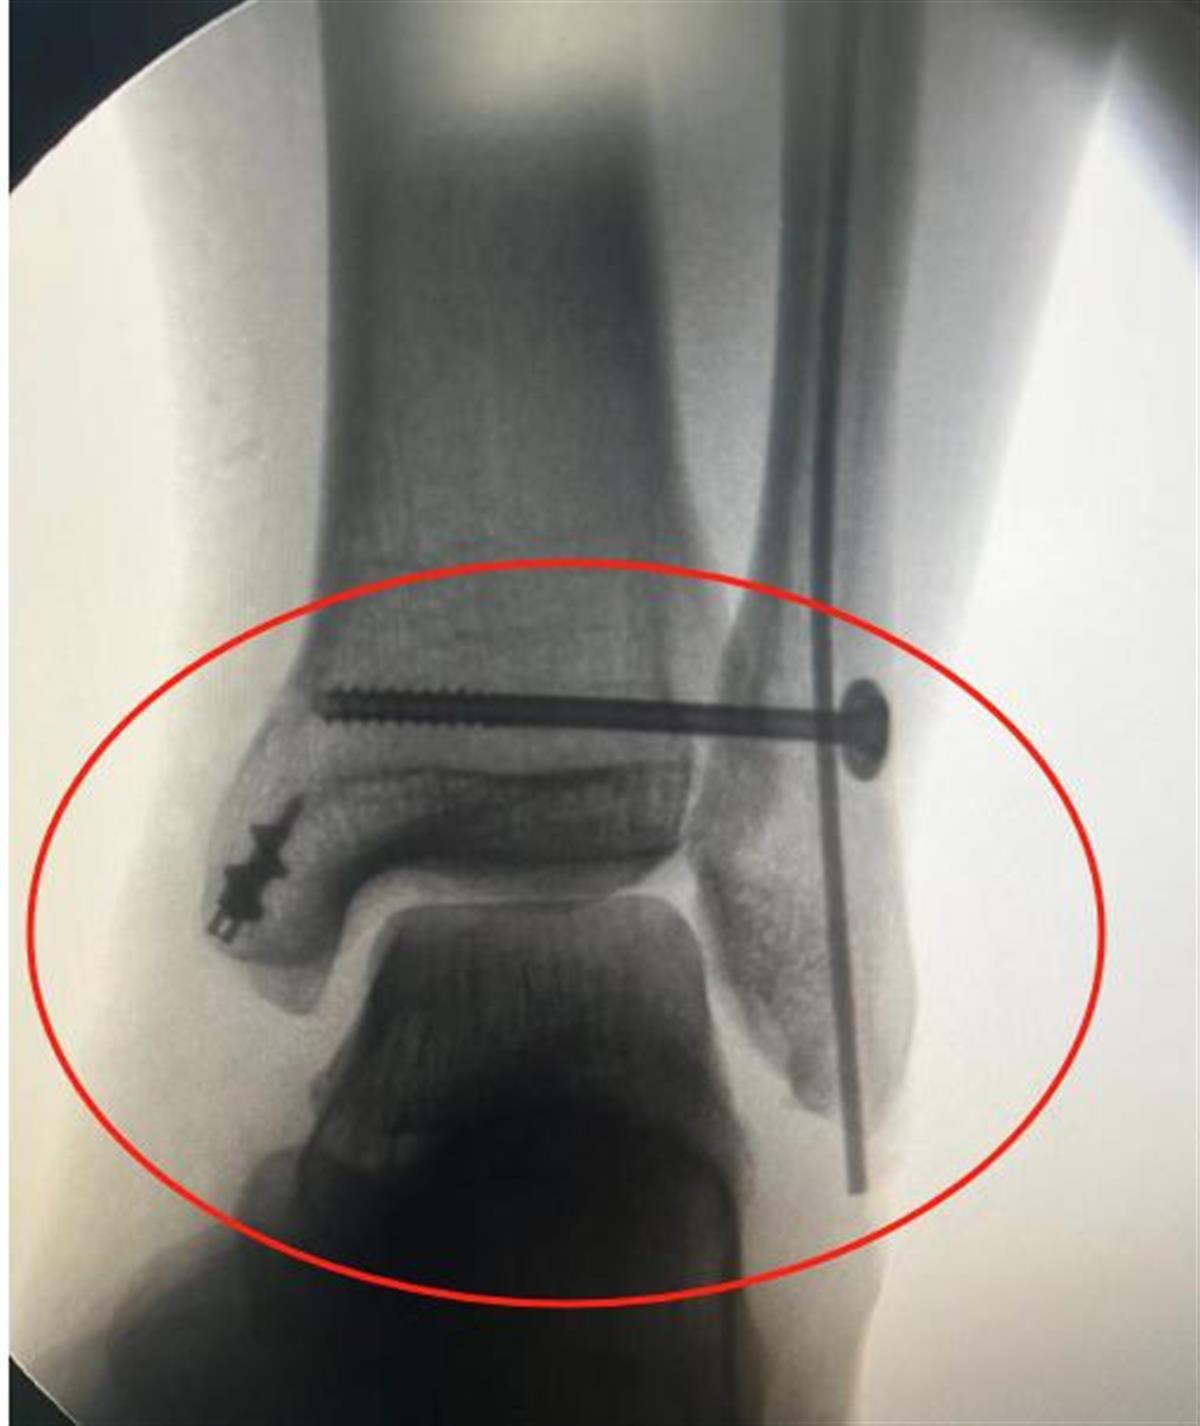

2月22日上午,创伤骨科医护团队为孔先生行踝关节修复手术,术中可见他的三角韧带浅层、深层完全撕裂,医生们仔细清除断裂凝血块,逐层切开皮下、筋膜后以血管钳行手法复位,配合髓内针旋转动作顺利将髓内针置入骨折近端髓腔。术后孔先生恢复良好,可以自行坐起并正常进食。

术后孔先生踝关节韧带修复内固定良好